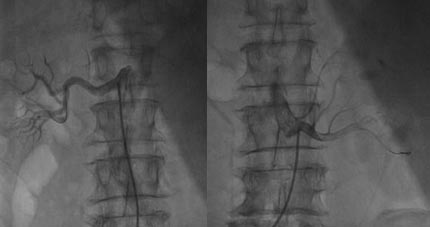

手术过程:医生在影像引导下,通过患者大腿根部的微小穿刺点,将一根细如发丝的导管送入肾动脉。随后,导管释放出温和的射频能量,对肾动脉外壁的交感神经纤维进行精确消融,从而从根源上降低交感神经的过度激活,实现长效降压。

近日,我院成功为一位饱受高血压困扰20余年的患者实施了首例RDN手术。患者为68岁男性,长期服用三种降压药,血压仍高达220/110mmHg,属典型的“难治性高血压”。同时,患者合并严重痛风,频繁发作的痛风性关节炎极大地限制了许多降压药物的选择和使用,治疗陷入僵局。经过蔡卢铭主任医师团队的全面评估,并与患者及家属充分沟通后,决定为其施行RDN手术。

手术在局部麻醉下顺利完成。术中采用系统性消融策略,力求达到最佳效果。手术即刻便观察到血压的显著下降:患者术前血压为172/93mmHg,术中最低降至143/78mmHg。术后返回病房,血压持续平稳回落,次日清晨已降至理想的130/80mmHg。这一变化令人鼓舞,为患者的长期血压管理打开了新局面。